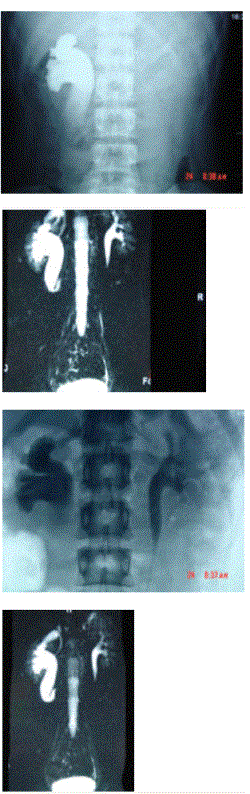

问题 男,20岁,右腰部胀痛不适,MR如图示,下列说法正确的是( )

选项 A、考虑为右侧腔静脉后输尿管 B、考虑为右侧输尿管自身的扭曲 C、右侧输尿管上段扩张积水 D、右侧输尿管走行异常,呈"S"形向中线移位 E、右侧肾盂积水

答案 ACDE